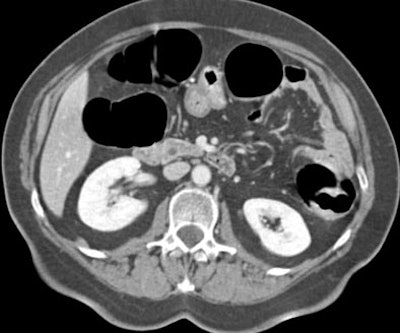

![]() |

| Transverse MDCT colonographic image after contrast material injection. An occlusive carcinoma 3 cm in diameter is identified within the descending colon. The lesion was correctly staged as T2 at CT. Image courtesy of Dr. Riccardo Iannaccone. |